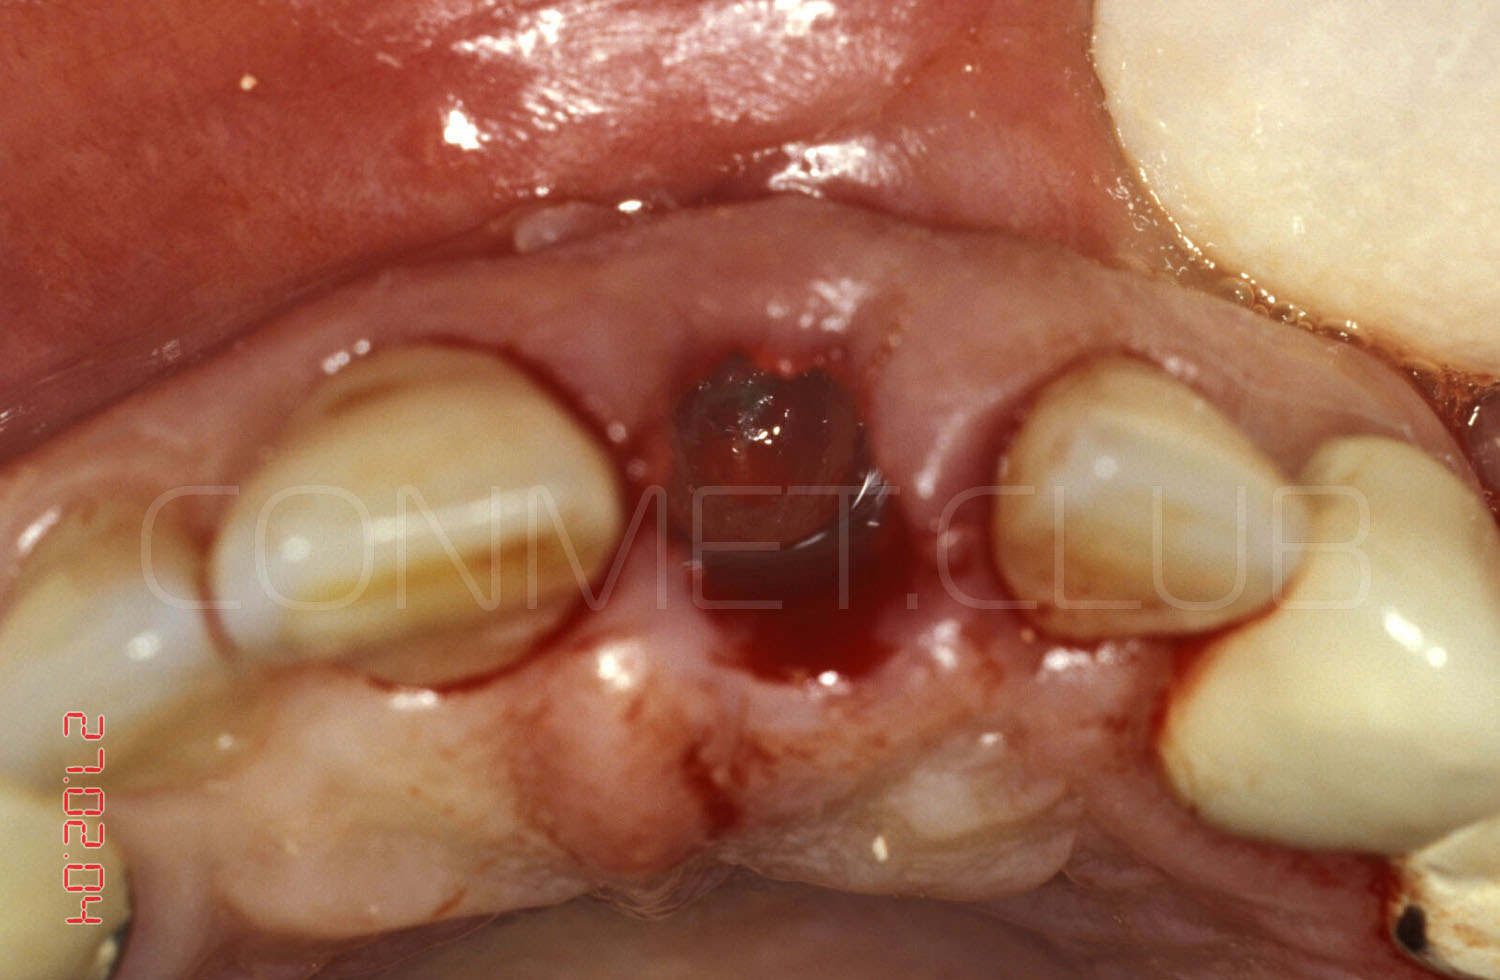

Вид на лунку удаленного зуба. Щипцы при удалении не использовались, только кюретажная ложка СМ 2/4 и прямой элеватор.

Сразу после экстракции зуба 21 производится установка имплантата КОНМЕТ с полированной трансгингивальной частью высотой более 3 мм. Интерфейс имплантата - просто конус Морзе и ни каких антиротационных шестигранников!

Имплантат установлен и зафиксирован винт-заглушка. Обратите внимание, что даже при столь широком экваторе имплантата не удалось полностью перекрыть диаметр костной альвеолы в направление зуба 11. Швы не накладывались и поверхность имплантата закрывалась мазью Солкосерил Дентал